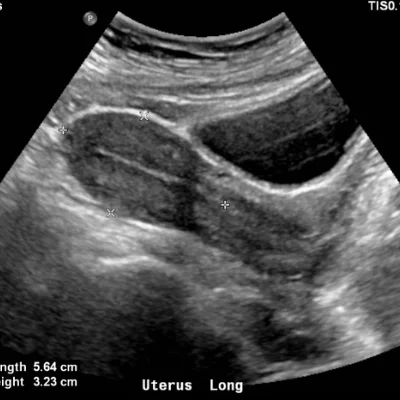

Pelvis

Uterus, ovaries, bladder, prostate

Follicular Study

For individuals undergoing fertility treatment or natural cycle monitoring, follicular studies track ovarian follicle development. These scans help determine ovulation timing and guide assisted reproductive procedures.